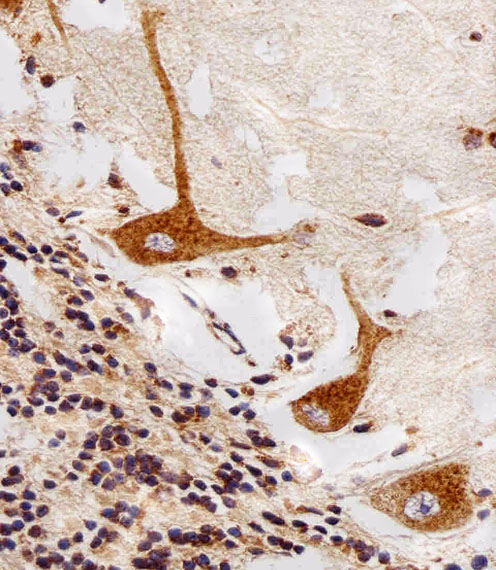

IHC 1/100-1/500 Human,Mouse,Rat

PPT1 (Palmitoyl-Protein Thioesterase 1) antibody is a tool for studying the PPT1 enzyme, a lysosomal hydrolase critical for cleaving thioester bonds in palmitoylated proteins. PPT1 deficiency causes neuronal ceroid lipofuscinosis type 1 (CLN1), a fatal neurodegenerative disorder characterized by lysosomal storage of autofluorescent material. The antibody enables detection of PPT1 expression levels in tissues and cultured cells, aiding research on CLN1 pathogenesis and protein depalmitoylation mechanisms.

As CLN1 primarily affects the nervous system, PPT1 antibodies are widely used in brain tissue analysis through immunohistochemistry and Western blotting. Recent studies also explore PPT1's role beyond neurodegeneration, including cancer progression and immune regulation, where its expression patterns correlate with disease outcomes. Commercial PPT1 antibodies are typically raised against specific epitopes of human PPT1. with validation in knockout models to ensure specificity.